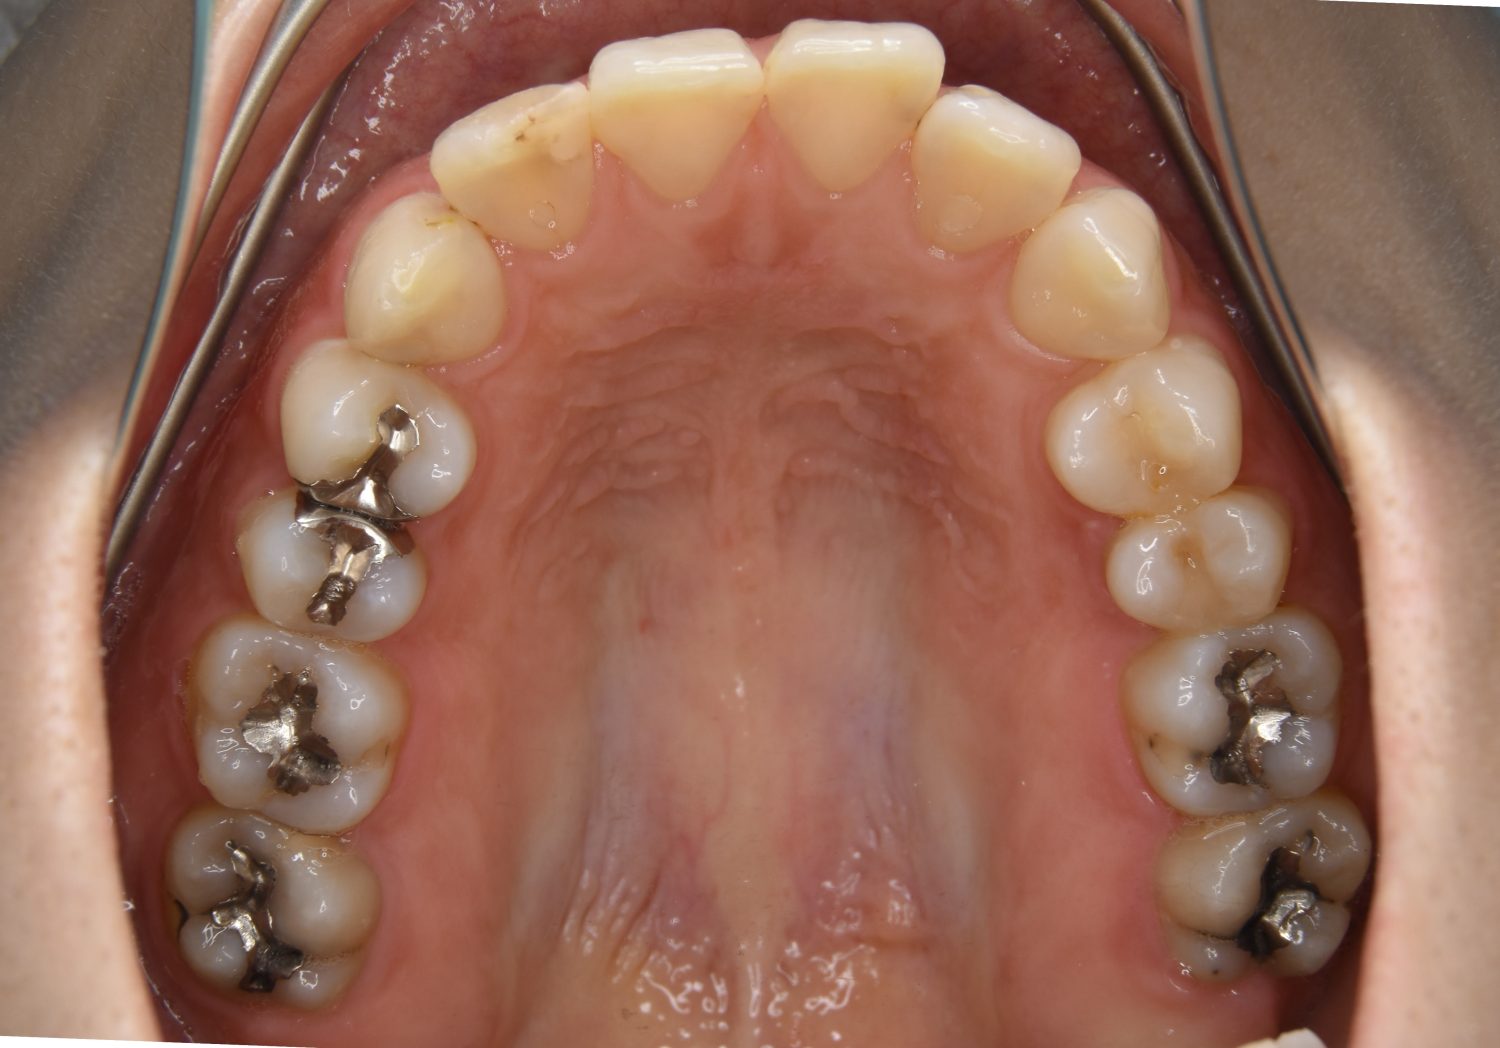

Before

上下前歯部に叢生(凸凹)が認められる状態でした。歯列の遠心移動を行うことで機能面および審美面が改善されました。